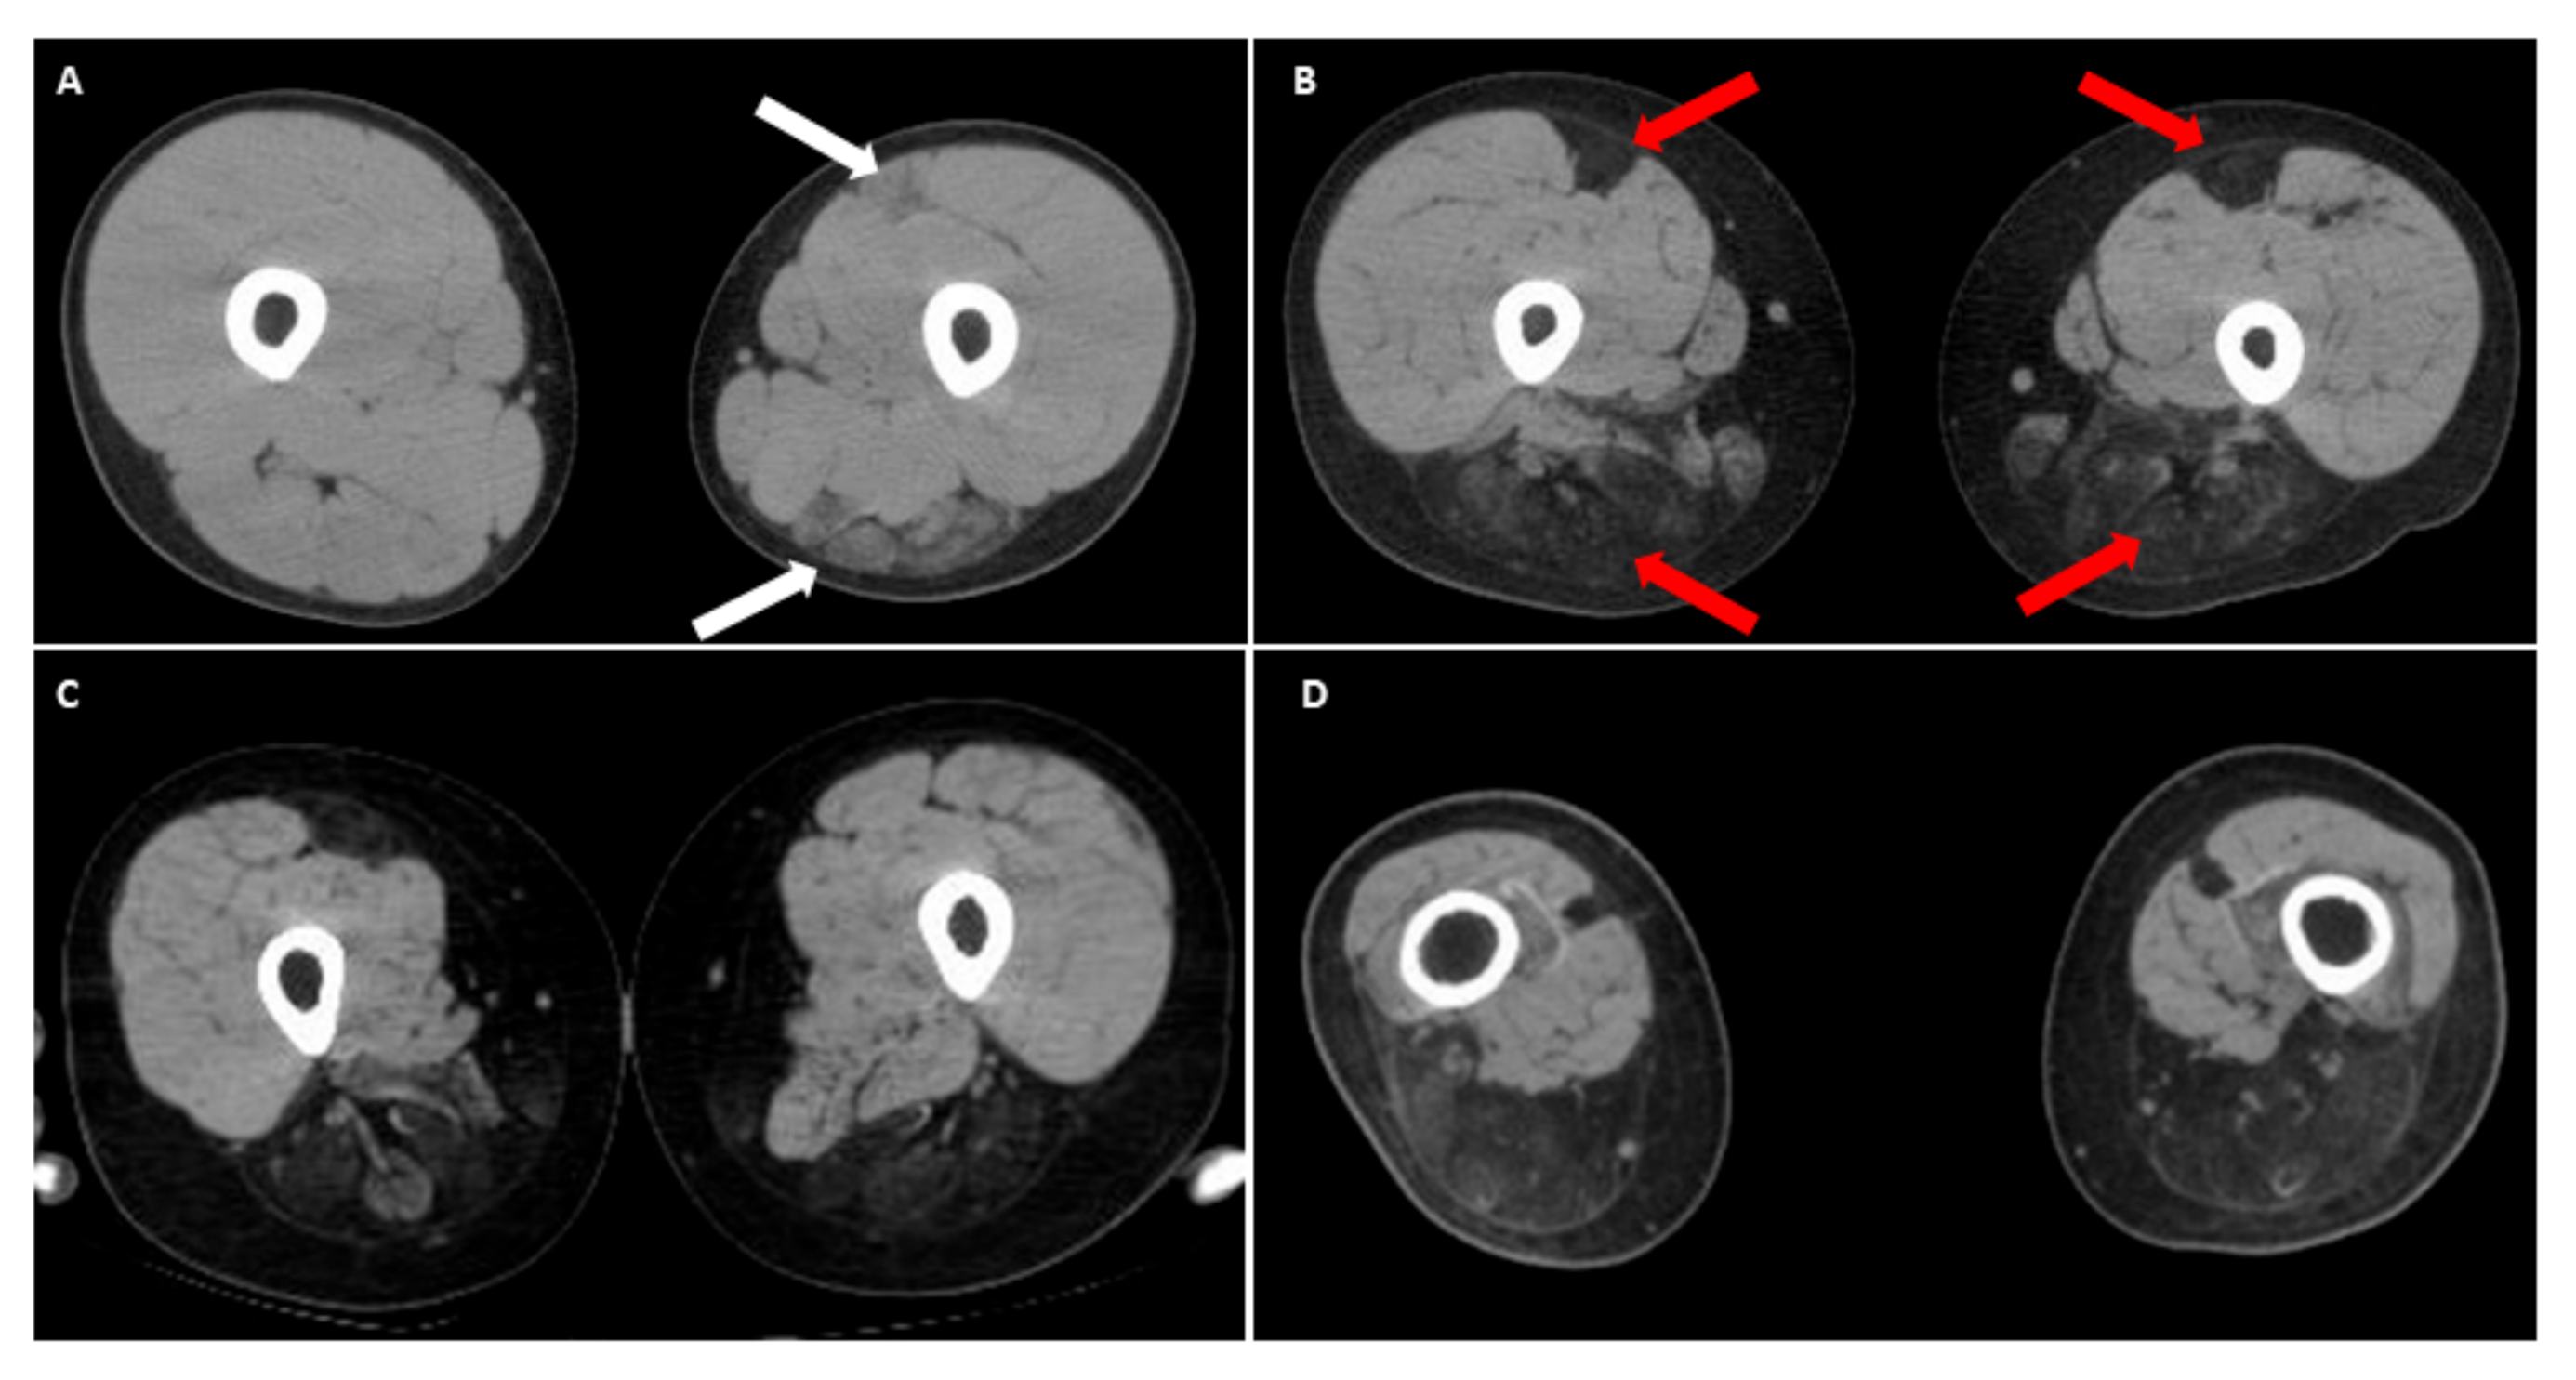

Recently, there have been emerging reports of the involvement of the lower limbs in the classic form of FSHD, especially in the hamstring and posterior calf muscles [36,37,38]. It is worth noting that in the anterior thigh muscle group (quadriceps), the rectus femoris seems to be more affected, especially in patients with early-onset FSHD [22,36]. We recently observed a peculiar thigh muscle involvement pattern in some patients with infantile FSHD who became wheelchair-bounded before 20 years of age. In the computed tomography (CT) image of their thighs, the selective degeneration of bilateral rectus femoris with relatively sparing other parts of anterior thigh muscles, accompanying dramatic wasting of hamstring muscles (Figure 3). Compared with other classical FSHD patients in our database, this special muscle imaging feature has never appeared at such a young age. As infantile cases are known to have a much faster disease progression, this unique pattern of muscular involvement may represent a “time-lapse picture” for classical FSHD with a slower disease course [10,16]. We suggest that this peculiar imaging finding of lower extremities in an FSHD patient may indicate a rapid motor function decline.

Figure 3.

Muscle computed tomography (CT) of upper thighs in infantile FSHD patients. (A) A male with 13 kb EcoRI showing early degeneration of left hamstring muscles and rectus femoris (white arrows) at 12 years old, compared to a relatively normal appearance of right thigh muscles; (B) Follow-up at 15 years old showing a rapid progression of muscle degeneration depicting a “wrench-head” appearance caused by extensive muscle wasting at the bilateral hamstring muscles with selectively affected rectus femoris of quadriceps (red arrows). Another two CT findings of (C) right leg of a 16-year-old female (11 kb EcoRI), and (D) both legs of a 28-year-old male (10 kb EcoRI), showing a similar muscle pattern, respectively. Informed consents were obtained from above reported patients.